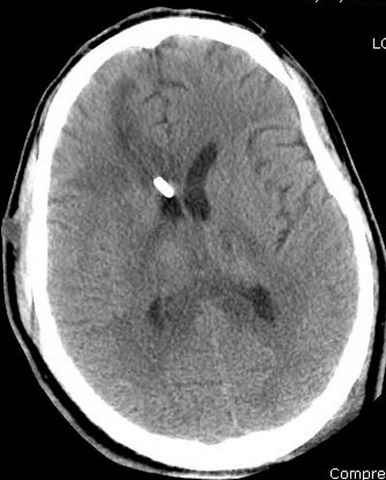

03.14.2005

больному 42, автоавария, политравма, открытая черепномозговая травма, безсознании, открытый перелом бедра, размозжение мягких тканей, дефект кожи на передней поверхности бедра около 13 см2 от ожога, компартмент синдром.

По поводу открытого перелома больной ургентно взят на ретроградное интрамедулярное штифтование, после рутинного дебрайдмента и фасциотомии на бедре и на голени.

Наблюдается службой травмы и нейрохирургии (ICP) Increased Intracranial Pressure by ventricular cateter

перелом бедра

монииторинг